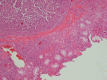

Schimke immuno-osseous dysplasia is a rare autosomal recessive multisystem disorder characterized by steroid-resistant nephrotic syndrome, immunodeficiency, and spondyloepiphyseal dysplasia. Mutations in SWI/SNF2 related, matrix associated, actin dependent regulator of chromatin, subfamily a-like 1 (SMARCAL1) gene are responsible for the disease. The present report describes, for the first time, a Schimke immuno-osseous dysplasia child with SMARCAL1 missense mutation (R561H) and manifestations of intussusception secondary to Epstein-Barr virus-negative non-Hodgkin lymphoma, who expired due to septicemia following chemotherapy. The report emphasizes the necessity of more limited immunosuppressive protocols in Schimke immuno-osseous dysplasia patients with lymphoproliferative disorders.